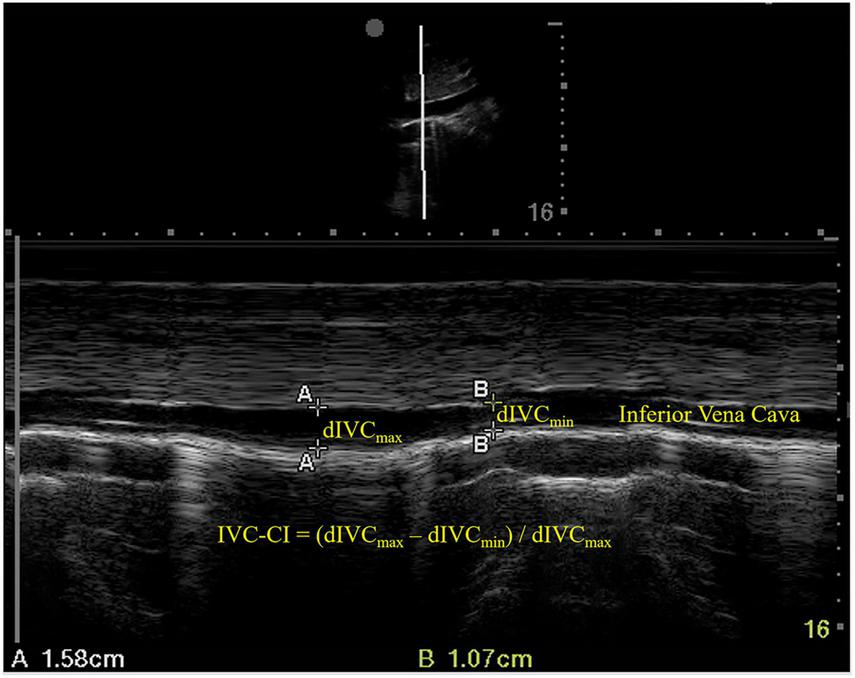

An ultrasound examination of the IVC was conducted immediately before anesthesia induction using a phased array probe (Sonosite Edge II) in M mode, with the patients in a supine position. The sampling site was placed 3 cm from the right atrium (Figure 1). dIVCmax (at the end of normal expiration) and dIVCmin (at the end of normal inspiration) were measured in three consecutive unforced respiratory cycles, and the results were averaged. IVC-CI was calculated as (dIVCmax–dIVCmin)/dIVCmax and expressed as a percentage (Figure 1).

FIGURE 1

Ultrasound measurements of the inferior vena cava. dIVCmax, maximum inferior vena cava diameter; dIVCmin, minimum inferior vena cava diameter; IVC-CI, collapsibility index of inferior vena cava.